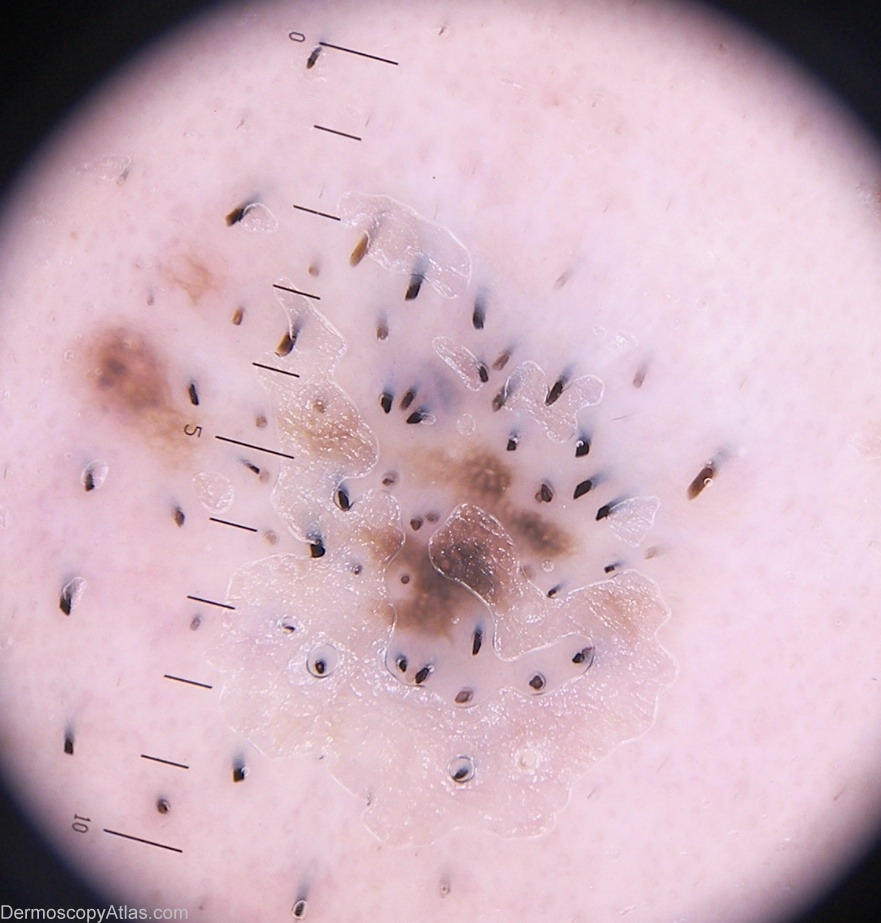

Site: Cheek

Diagnosis: Nevus recurrent

Sex: M

Age: 38

Type: Heine

Submitted By: Stelios Minas

History: According to the patient this lesion present for a long time. A year ago the lesion excised with laser. Some time after he has developed a new lesion precisely at the excision site. No previous histopathology report (laser excision). We excised it(surgery) imediatly after that patient told me the word "laser". The final hstp report was a Compound nevus. I always have in my mind the Tiger Melanoma. Tiger Melanoma is type of Melanoma which develope after laser excision. Laser excision is not recommended for melanocytic lesions! Dermoscopic description: Atypical network.